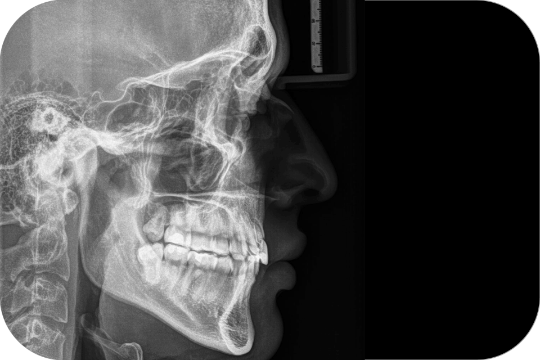

Cefalométrica